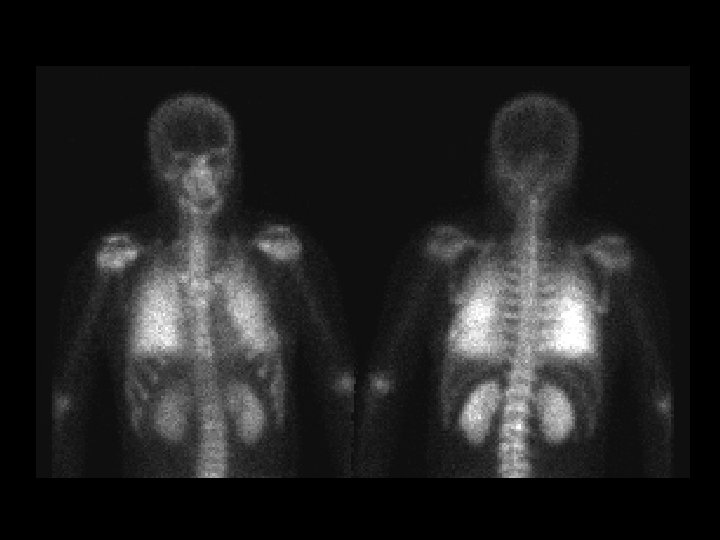

Tuberculosis & AIDS • • • Ga-67 citrate 5 -10 m. Ci, i. v. images obtained at 72 hrs diffuse lymph node activity in the chest & abd intense splenic activity gallium binds transferrin (liver) and lactoferrin (salivary and lacrimal glands, nasopharynx, spleen, and bone marrow) ddx: – lymphoma – sarcoid – infection (abscesses)